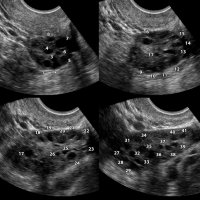

Polistik Over Sendromu

Stein-Leventhal sendromu ya da yaygın olarak bilinen adı ile polikstik over sendromu (PKOS), en sık 30 yaş altı kadınlarda görülen ve overde kalın bir over dokusu içinde iyi huylu birçok kist ile karakterize bir hastalıktır.